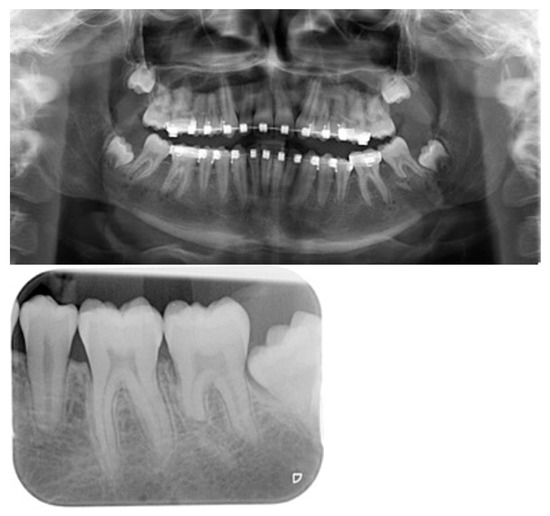

All patients achieved a Class I occlusion, which remained stable until the data collection of this publication. Infections that would have led to premature distractor removal were not observed. However, in one patient an abscess in the region of the activation rod had to be treated by evacuation. No functional impairment of the sensitive function of the third branch of the trigeminal nerve was noted. In nine patients, fractures of the mesial root of the second molar occurred at different levels during osteotomy (Figure 6). Three second molars had to be removed, one molar with root fracture was treated endodontically. Resorptions of the fractured root fragments were seen during follow-up.

Figure 6.

Postoperative x-ray documentation of an unintentional root tip amputation in the second molar in the left mandible during an IMDO treatment. Consolidation of the root stump with resorption of the root fragment.